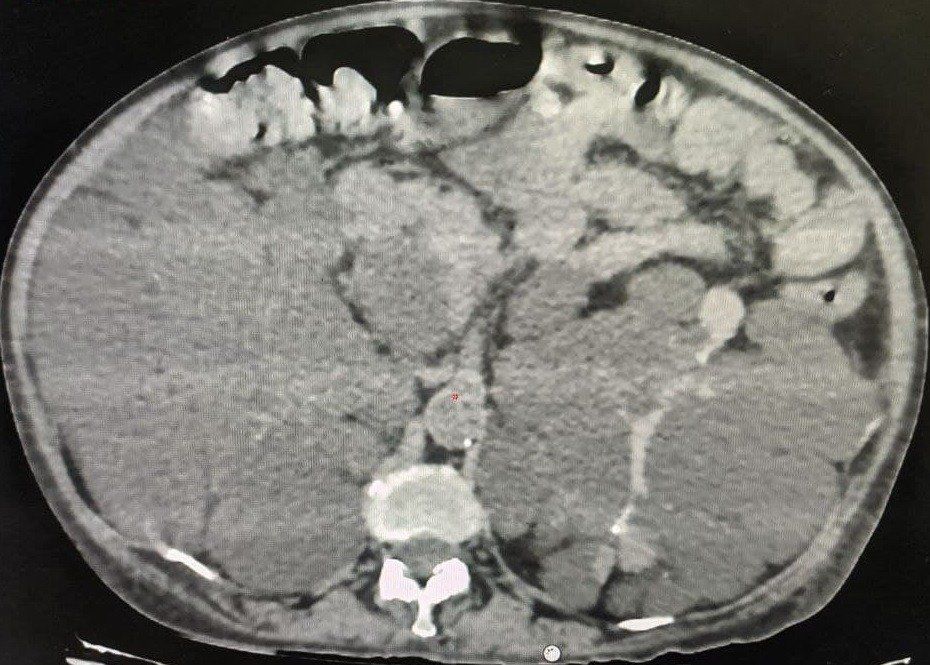

40 year old male with idiopathic chronic pancreatitis presented with intractable pain, sitophobia with severe weight loss (adult male weighs 29 Kg) and history of recurrent episodes of GI bleed. He also has CKD (cr1.7) related to neurogenic bladder. Patient was shifted to us in shock with HB 3 gm % and massive GI bleed. MRI and CT angio showed a large 6x5 cm Pseudoaneurysm in uncinate process of pancreas probably arising from inferior pancreaticoduordenal artery causing hemosuccus pancreas. In view of CKD we chose to tackle aneurysm by direct glue embolisation of aneurysm sac to avoid the high volume contrast of conventional angio (image) Pt was put on NJ feeds in view of severe malnutrition secondary to intractable pain and sitophobia. Post embolisation 2 months later he came back with weight gain of 8 kg and a stable Hb%. His Repeated CT scan showed a persistent intrapancreatic head cyst with dilated pd in body and tail. The aneurysm cavity filled with glue cast has shrunk to almost one fifth the initial size. In view of large duct disease with Pseudoaneurysm we decided to go ahead with a whipple pancreaticoduodenectomy. The post op specimen shows the intrapancreatic cyst and the glue cast of the aneurysm (yellow arrow). His recovery was uneventful and is completely pain free post procedure.